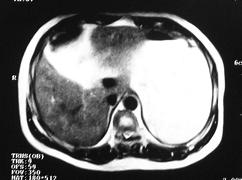

男 45岁。体检b超发现肝脏一低密度病变,怀疑是血管瘤,来ct检查。

ct平扫:在肝右后下叶一直径约2厘米的圆形低密度病变,ct值约32hu。

增强三期都未强化。后经mri检查,t1wi及t2wi为等信号,与肝脏等信号。